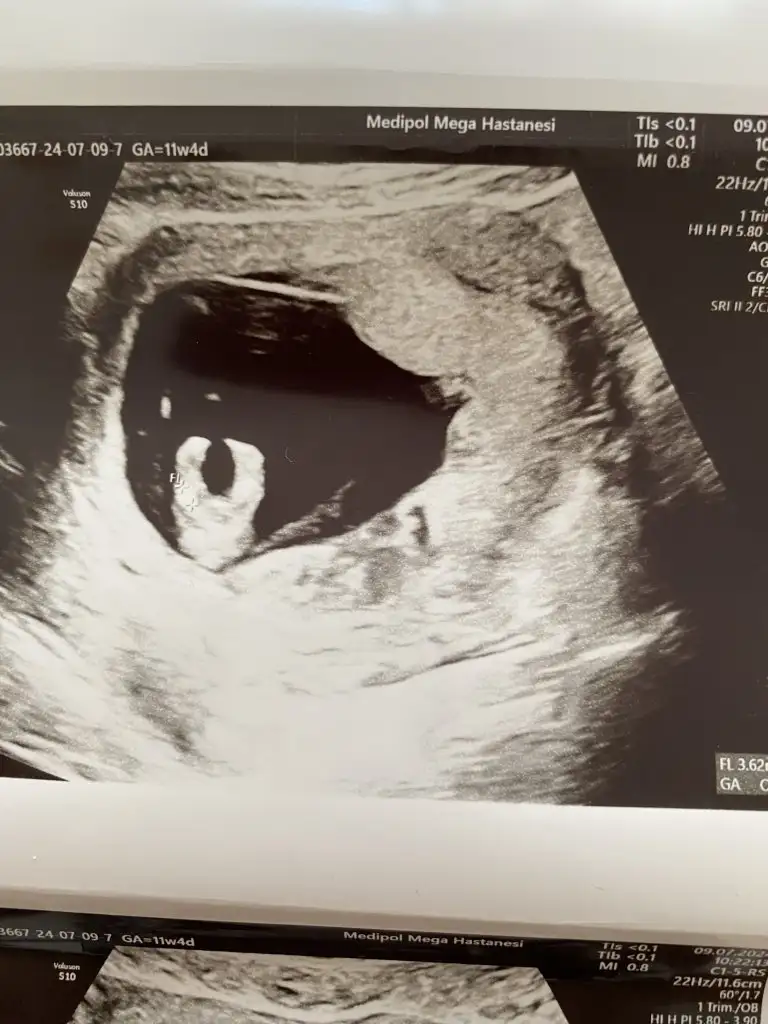

Ben de dün kontrole gittim 11+4te. Uyuyordu benimki de, doktor biraz rahatsız edelim dedi ama yok uyandırmadıkKuzum doktor öyle dedi zaten gittim meyve suyu içtim bişeyler yedim çok su içtim gittim uyanmadı bazı bebekler böyle olur dedi 22. Haftaya kadar hem göstermez hem hareketsiz olur dedi bakalım senin nasıl geçecek

Ayy bacak arası 3cizgi mi var bana mı öyle geliyor.genelde takip ettiğim Dr lar 3cizgide kız diyorlar.Bu arada doktor cinsiyet için daha erken ama şimdilik bacak arasında bir çıkıntı vs görünmüyor dedi. Sizler ne dersiniz kızlar